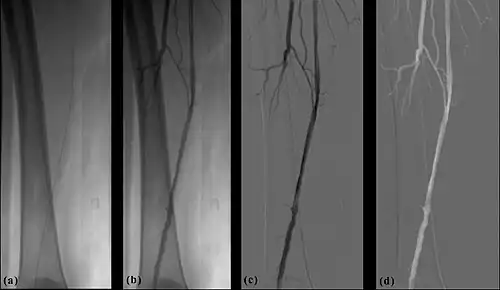

- Additional processes involve Bolus Chasing, Rotational Angiography and Volume Tomographic Angiography. Bolus Chasing[28] has been found to be particularly helpful in peripheral angiography, for example. Here, the progress of the contrast medium is tracked automatically and used to increment the table and/or XRT/image receptor movement to the next anatomical region. The subsequent set of subtraction images can then be used to construct a composite image of the peripheral vasculature. In Rotational Angiography[29], a C-arm assembly, for example, can be caused to rotate at 10 - 30 degrees per second during the imaging sequence. Subsequent dynamic display of the subtraction images can be used to generate a perceived 3D presentation so that complex relationships within the vasculature can be more readily appreciated. Volume Tomographic Angiography[30] is similar to Computed Tomography (CT) where the C-arm is rotated around the patient during the imaging sequence. The image data is subject to a volume reconstruction algorithm which permits generation of three-dimensional images of the opacified vasculature. We will consider this latter process in more detail below.